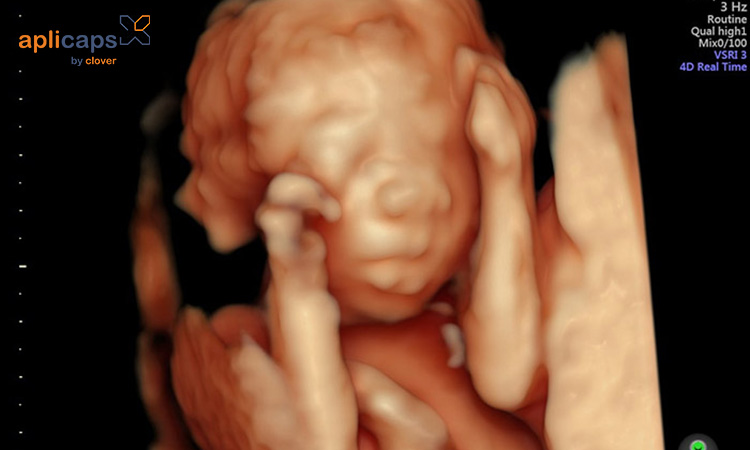

Thai 20 tuần tức là em bé và mẹ đã bên nhau 5 tháng. Mẹ lúc này đang trong tam cá nguyệt thứ hai của thai kỳ và đã đi được nửa chặng đường. Thời điểm này là giai đoạn phát triển mạnh nhất của thai nhi. Mẹ đã có thể cảm nhận được từng cử động của bé.

Sự phát triển của thai nhi ở tuần thứ 20

Ở tuần thai thứ 20, thai nhi đã cơ bản hình thành đầy đủ bộ phận. Em bé lúc này có chiều dài khoảng 16,5cm và kích thước tương đương với quả xoài. Khác biệt lớn nhất là tại thời điểm này, những dấu vân tay, lòng bàn tay, bàn chân của trẻ được hình thành. Tóc của thai nhi cũng được mọc ra nhiều hơn.

Tiểu não của trẻ cũng không ngừng phát triển. Đây là cơ quan quan trọng với thần kinh vận động, nhận thức và cảm xúc của trẻ. Ngoài ra, cơ thể trẻ cũng được bao phủ bởi một lớp chất gây màu trắng. Chất này có vai trò quan trọng trong việc bảo vệ làn da của trẻ không bị kích ứng trong nước ối. Ngoài ra, nó cũng giúp trẻ chuyển động dễ dàng và giúp quá trình sinh dễ dàng hơn. Đặc biệt, vào tuần thứ 20, em bé đã bắt đầu chuyển động và có những cú huých mạnh mẽ vào bụng mẹ.